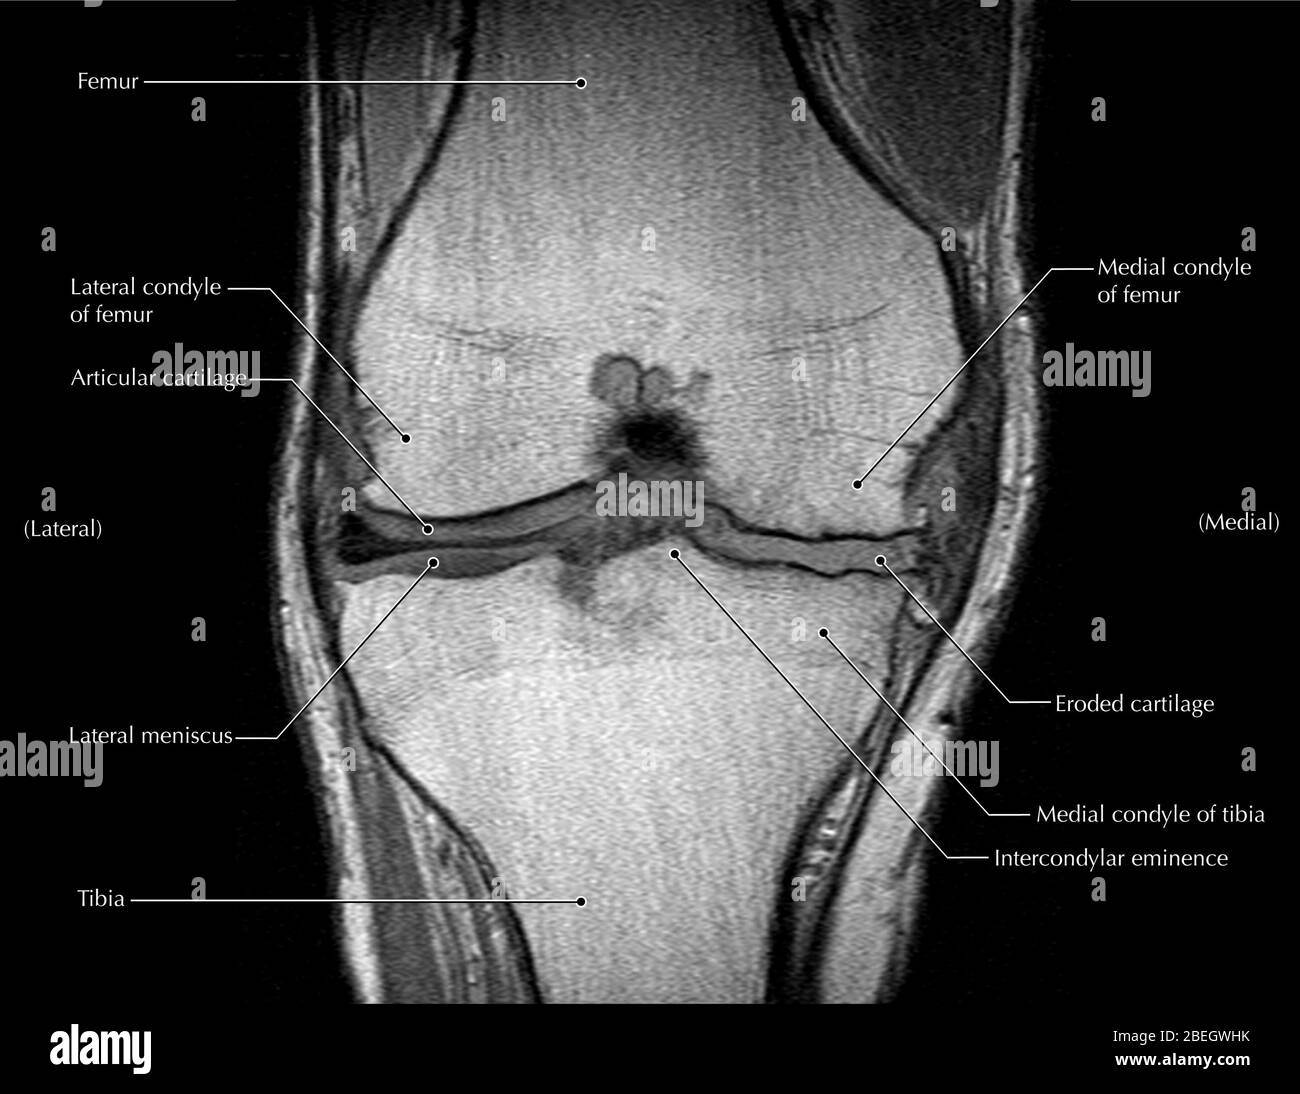

MRT Knie – DocCheck MRT Niere3 – DocCheck

MRT: Knie – DocCheck MRT in der Krebsmedizin

MRT: Knie – DocCheck MRT Schädel – DocCheck

MRT: Knie – DocCheck MRT Knie links